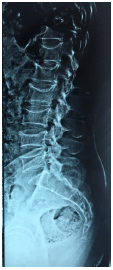

Na Osteoporose, as fraturas vertebrais são o tipo mais comum de fratura e estão associadas com deformidade, perda de altura, dorsalgia, lombalgia crônica ou aguda, alterações pulmonares decorrentes da modificação da caixa torácica, aumento da morbidade e mortalidade. De acordo com a classificação de fratura vertebral por análise semiquantitativa de Genant, na radiografia simples de coluna lombar em perfil apresentada na imagem abaixo, podemos classificar tal fratura como: